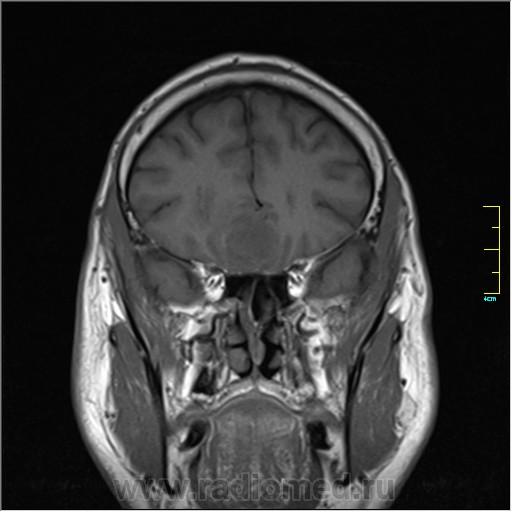

Пациентка направлена на исследование с диагнозом "Гипертонический криз", энцефалопатия неуточненная.

Cor T1:

частично функционирующая аневризма

Иначе говоря, аневризма с хронической геморрагией, т.к. мы видим фракции крови различного возраста.

По-моему, аневризма с пристеночными тромбами.

Постепенное пристеночное образование тромбов приводит к появлению типичного для аневризмы феномена -слоистости МР сигнала в полости аневризмы. Данная картина демонстрирует слоистый характер тромботических масс в полости аневризмы .Функционрирующая часть имеет низкий сигнал во всех режимах сканирования. Дополнительно-перифокальный отек.

А может более корректно интерпретировать как частично тромбированная аневризма... Уж коь речь идет о фракциях, ну то есть о тромбе по сути.... Ну и плюс перфокальный отек головного мозга (вероятнее цитотоксический+вазогенный).